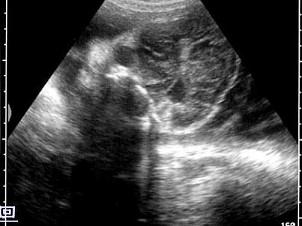

晚孕胎儿脑部声像图,最可能的诊断是?(?)A.正常声像图B.淋巴管囊肿C.脑膜膨出D.脑积水E.露脑畸形

问题 晚孕胎儿脑部声像图,最可能的诊断是?(?)

选项 A.正常声像图 B.淋巴管囊肿 C.脑膜膨出 D.脑积水 E.露脑畸形

答案 E